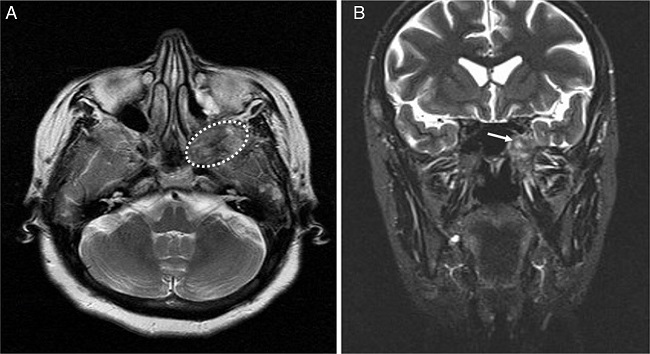

In MRI, dense-heterogeneous contrasted mass was detected and it was mildly hyperintense on the T2-weighted images and hypointense on the T1-weighted images (Fig. 2).

Preoperative CT and MRI are useful in defining the location and extension of hemangiomas. CT findings of the cavernous hemangiomas are a soft-tissue density circumscribed mass, and also enhancing after injection of contrast. Hemangiomas of nasal cavity and paranasal sinuses may cause some changes on the adjacent bone. Generally, these changes seem like benign on imaging modalities. Dillon et al. reported three of six patients with cavernous hemangioma of nasal cavity have adjacent bone changes. In addition, all three cases have benign changes consisting of remodeling and expansion.5 On the other hand, hemangiomas demonstrate an iso or hypointense signal on T1-weighted MRI and an hyperintense signal on T2-weighted imaging. Also, these tumors show intense contrast enhancement.10